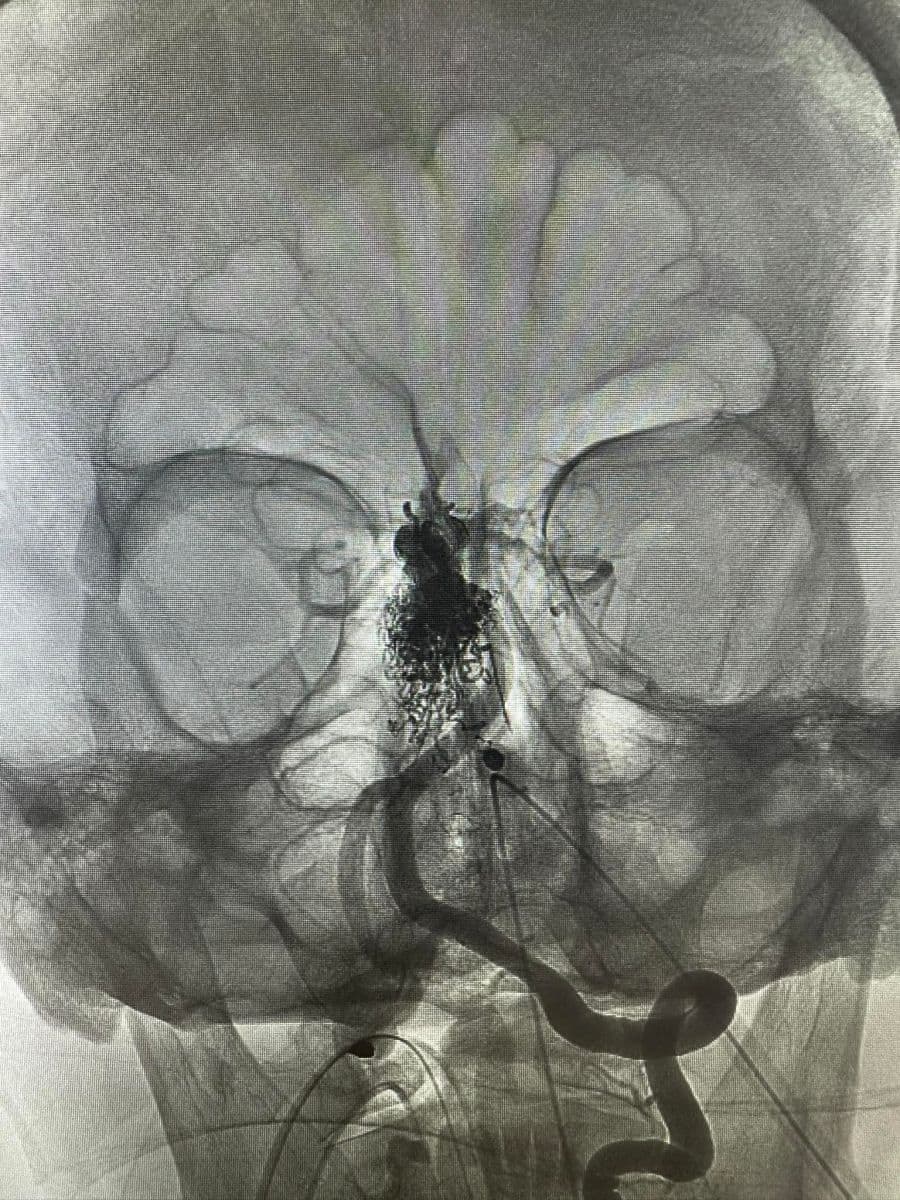

Δια ζώσης συμμετοχή των φοιτητών του Πανεπιστημίου Πατρών σε εξειδικευμένες τεχνικές ενδοαγγειακής αντιμετώπισης αγγειακών δυσπλασιών του κεντρικού νευρικού συστήματος.

Στην επέμβαση συμμετείχαν ο Καθηγητής Ενδοαγγειακής Νευροχειρουργικής Κος Β. Παναγιωτόπουλος, ο Καθηγητής Επεμβατικής Νευροακτινολογίας κος Π. Ζαμπάκης, ο επιμελητής επεμβατικής ακτινολογίας κος Μ. Θεοφάνης και ο αναισθησιολόγος κ. Γούδας.